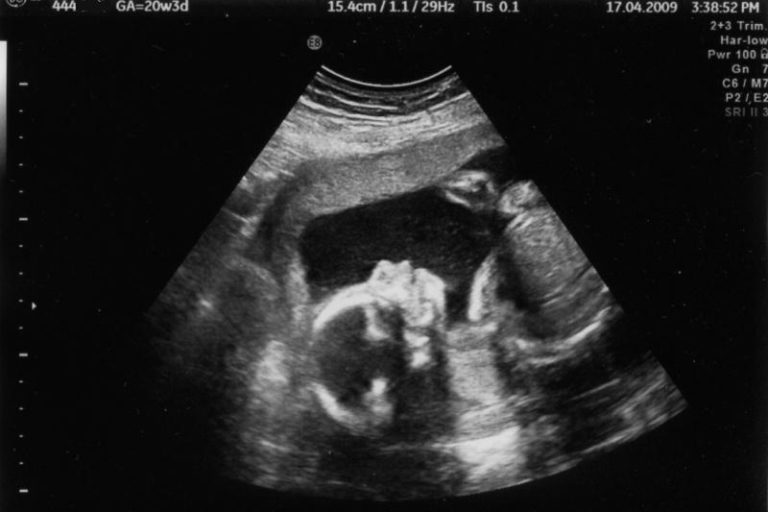

Со особена чест и задоволство ве известуваме дека повторно ја возобновуваме школата за психофизичка подготовка на трудници на ЈЗУ Универзитетска клиника за гинекологија и акушерство, како и можноста за безболно породување. Се во врска со Школата за трудници низ интервјуто со проф. д-р Ирена Алексиоска Папестиев, директорка на Универзитетската клиника за гинекологија и акушерство. СЛЕДЕТЕ…